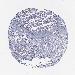

OVARIAN CANCER - Protein expressioni

A mouse-over function shows sample information and annotation data. Click on an image to view it in a full screen mode. Samples can be filtered based on level of antibody staining by selecting one or several of the following categories: high, medium, low and not detected. The assay and annotation is described here.

Note that samples used for immunohistochemistry by the Human Protein Atlas do not correspond to samples in the TCGA dataset.

Antibody stainingi

Antibody staining in the annotated cell types in the current human tissue is reported as not detected, low, medium, or high, based on conventional immunohistochemistry profiling in selected tissues. This score is based on the combination of the staining intensity and fraction of stained cells.

Each image is clickable and will lead to virtual microscopy that enables deeper exploration of all samples and also displays staining intensity scores, fraction scores and subcellular localization as well as patient and tissue information for each sample.

Antibody HPA051282

Cystadenocarcinoma, serous, NOS